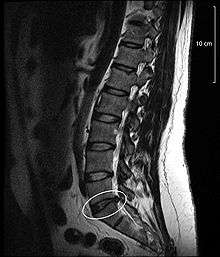

Disc protrusion

A disc protrusion is a disease condition which can occur in some vertebrates, including humans, in which the outermost layers of the anulus fibrosus of the intervertebral discs of the spine are intact, but bulge when one or more of the discs are under pressure.

Many disk abnormalities seen on MRI that are loosely referred to "herniation" are actually just incidental findings. These may be unrelated to any symptoms and are just bulges of the annulus fibrosus. Jensen and colleagues, in an MRI study of the lumbar spine in 98 asymptomatic adults, found that in more than half, there was a symmetrical extension of a disc (or discs) beyond the margins of the interspace (bulging). In 27 percent, there was a focal or asymmetrical extension of the disc beyond the margin of the interspace (protrusion), and in only 1 percent was there more extreme extension of the disc (extrusion or sequestration). These findings emphasize the importance of using precise terms in describing the imaging abnormalities and evaluating them strictly in the context of the patient's symptoms.[1]

A disc protrusion may progress to a spinal disc herniation, a condition in which there is a tear in the anulus fibrosus.